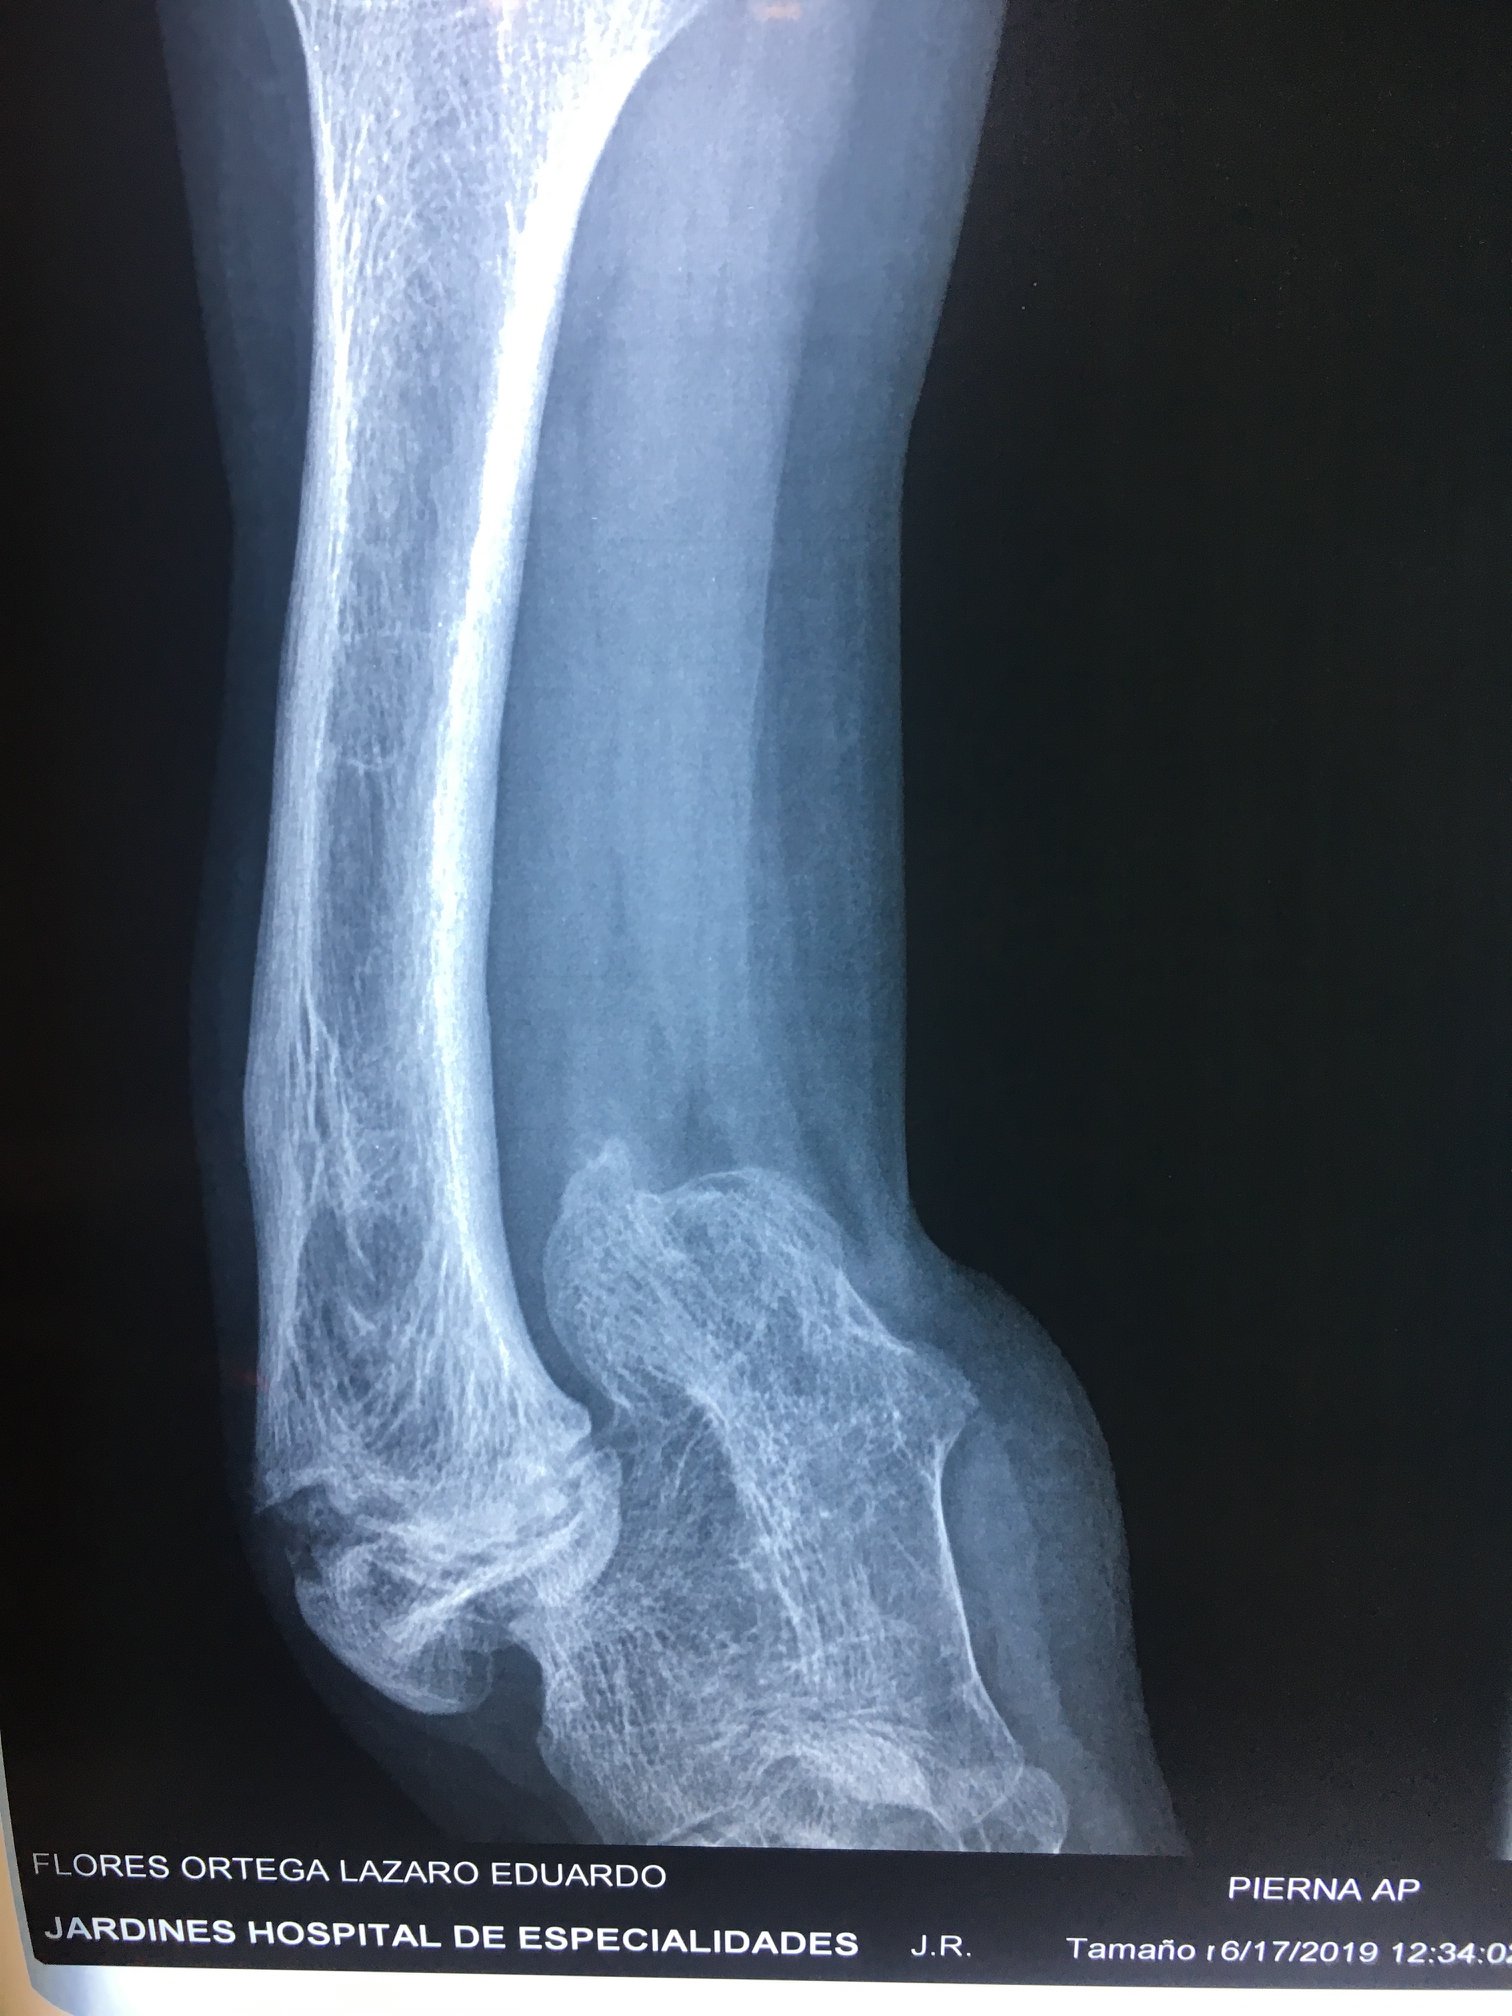

Ausencia congenita del peroné

A los papás de Lazarito les dijeron en Estados Unidos que la única alternativa para su hijo era una amputación; buscando segundas opiniones, llegaron conmigo. Lazarito, de 13 años, tiene #hemimelia #perónea, una ausencia congénita del peroné que causa malformaciones y acortamientos. Para evitar la amputación, se le realizó una reconstrucción del tobillo y alineamos su pierna de forma funcional. Ahora, mi pacientito ya camina con apoyo al 100%, realiza sus actividades diarias y dice que empezará a jugar fútbol. Agradezco a sus papás por la confianza y a sus familiares en Guadalajara por recomendarlo conmigo.